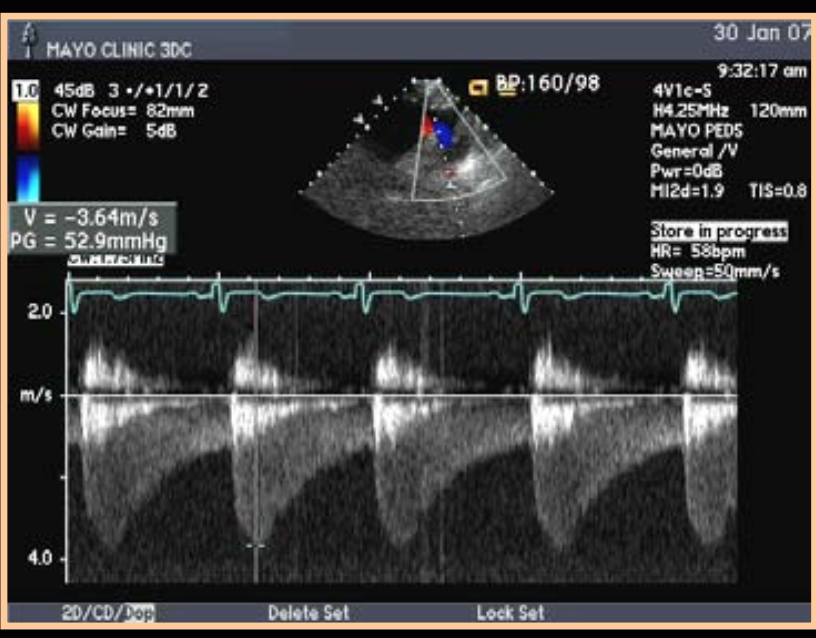

Diagnosis of this descending Ao doppler?

Coarctation